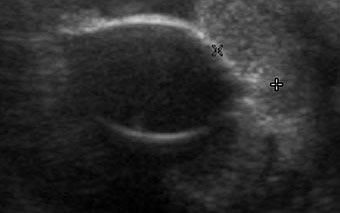

EYES

• Ultrasound is very useful in imaging retrobulbar masses and

assessing intraocular masses, retinal detachment and congenital

eye abnormalities.

Ocular tumour in the anterior chamber of the eye